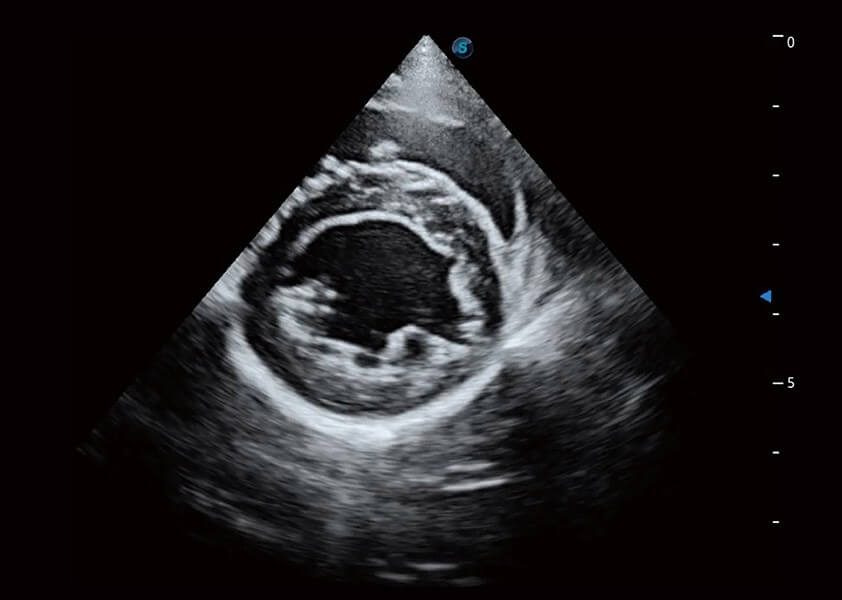

ProPet 60 作为一款高端台式动物超声设备,为动物医生的日常诊断提供了一系列贴合动物临床需求、解决临床实际问题的高级成像功能。凭借全系列高清探头,满足医生对腹部、心脏、生殖、浅表、肌骨等成像的所有需求,切实帮助您提升检查效率,提高诊断信心。

动物是人类最亲密的朋友和最值得信赖的伙伴。1xBET也一直致力于探索动物专用的超声影像解决方案。 全新推出的ProPet系列,是1xBET在动物超声影像智能化、专业化、精准化的一次跨越式革新。动物不能用言语来表述自己的不适,通过超声影像,ProPet系列搭建了动物医生与不同物种沟通的“桥梁”,为动物医生注入了“治愈之力”。